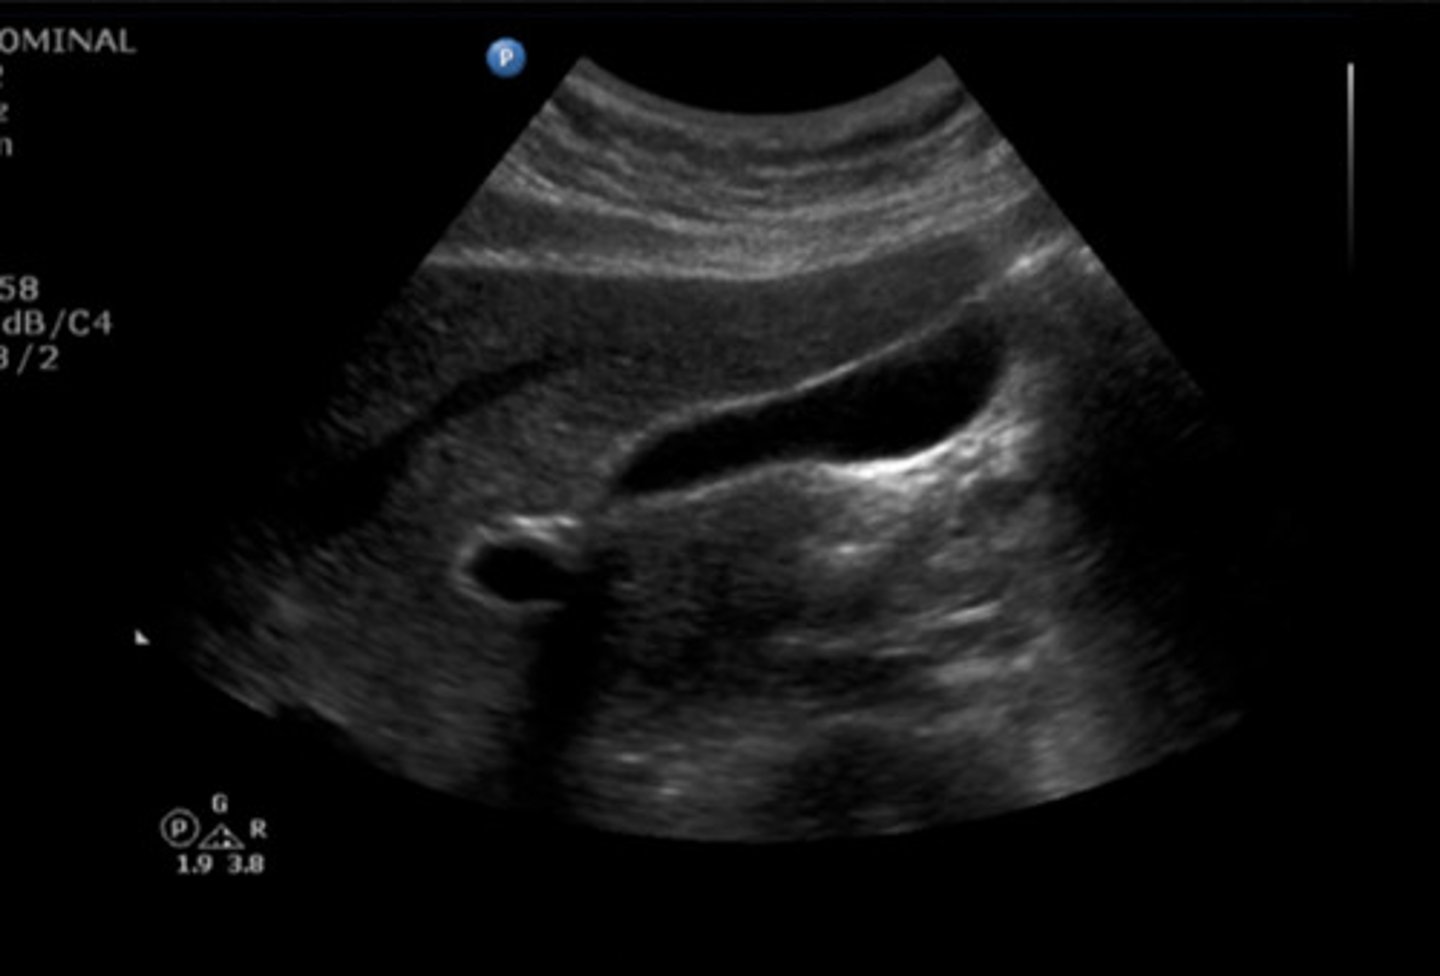

SAG GB RT LAT SUPINE

Identify the following;

SAG GB MID SUPINE

SAG GB LT LAT SUPINE

TRV GB FUNDUS SUPINE

TRV GB BODY SUPINE

TRV GB WALL SUPINE

Identify the following

TRV GB NECK SUPINE